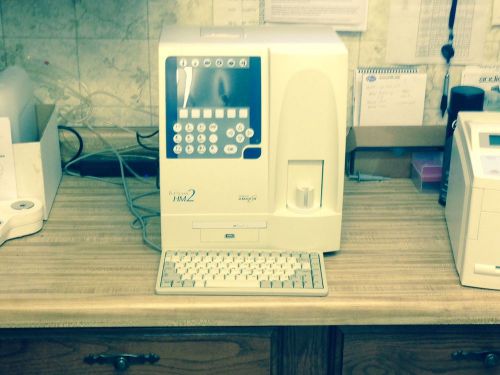

Abaxis HM2 Hematology Analyzer